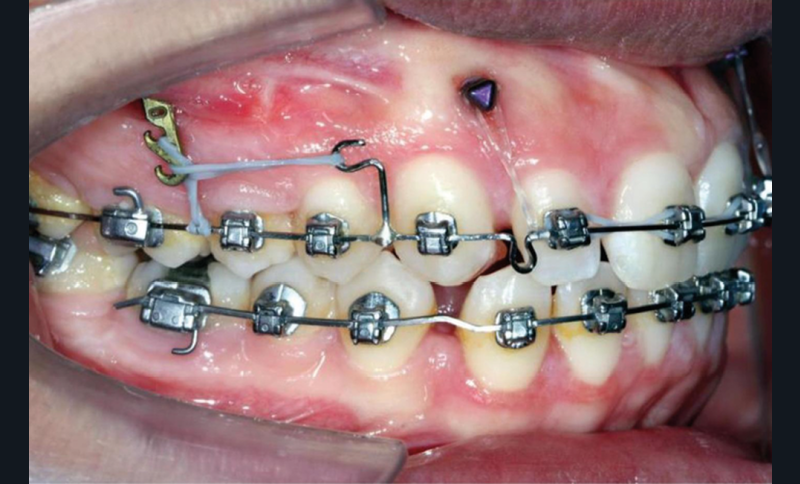

À côté de la coopération moindre qu’ils exigent, les ancrages squelettiques présentent également l’avantage de répondre à des indications très variées : correction des sourires gingivaux (Dr Skander Ellouze, fig. 3a-c), distalisation ou mésialisation molaire, supports pour les masques faciaux, mini transpalatin sur vis après expansion, ressorts de rétraction pour mettre en place les canines incluses sans léser les racines des dents adjacentes [3] (Dr Stéphane Renger, fig. 4) ou appareils d’expansion maxillaire (Dr Hans Winsauer, Dr Guido Sampersmans, fig. 5a-c)…